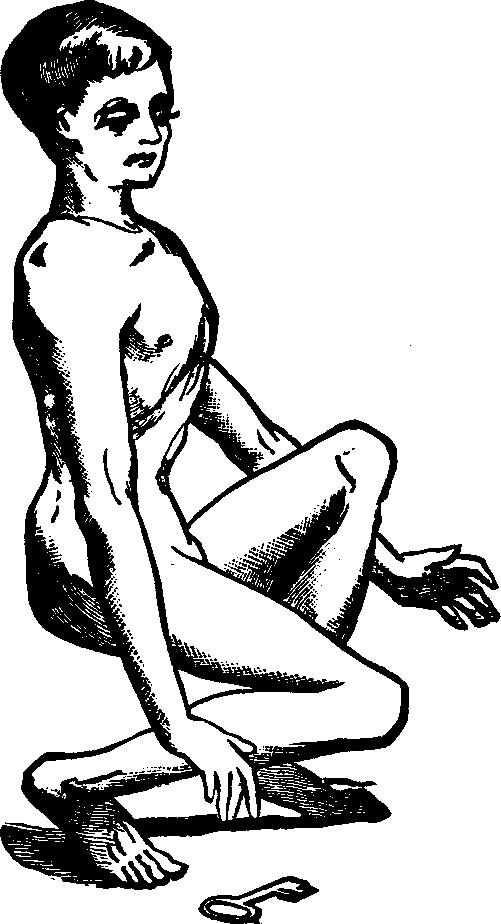

Absence of the Ovaries. Let us suppose the case of a young woman who has fully reached the period of puberty without having menstruated. All the organs which we have described, are manifestly developed, she is healthy, vigorous, robust, and able to exercise freely or to engage in laborious occupations. But we notice that her voice is not sweetly feminine, nor is her presence timid, tender, and winning; there is wanting that diffident sexual consciousness, which gently woos, and, at the same time, modestly repels, and tends to awaken interest, curiosity, and desire. Considering also that she has never manifested any inclination to menstruate, we are irresistibly led to the conclusion that the ovaries are wanting; the delicate mustache upon the upper lip, the undeveloped breasts, the coarse features, and her taste for masculine pursuits, all concur in this diagnosis. Thus we account for the harshness of the voice, fitted for command rather than to express the mellow, persuasive cadences of love. Such a malformation cannot be remedied.

Chronic Decline, with its attendant anæmia, may be induced by bad habits, destitution, or constitutional depravity. Sickly forms, wrecks of health, address our senses on every side. All these subjects evidently once had a capital in life, sufficient, if properly and carefully husbanded, to comfortably afford them vital stamina and length of days. Alas! they have squandered their estate, perchance in idleness and luxurious living, or have wasted it in vanities or misdirected ambition. Having become bankrupts in health, there is necessarily a failure of the menstrual function, and then follows a panic. All the blame of the insolvency and general derangement, is unjustly attributed to the non-performance of the duties of the uterus. Thus, this organ is altogether dependent Upon the general health for its functional ability, yet frequently treatment is instituted to compel menstruation, regardless of the condition of the system. Thus the enfeebled uterus is wrongfully held responsible for general disorder, because it ceases to act, when by acting it would further deplete the blood and thus materially contribute to the already existing chronic decline.

No matter what are the causes of this decline, whether they are the follies of fashion, the effect of indolence, debility in consequence of insufficient food, perversion of nutrition by irregular habits, lack of exercise, [pg 690]or the taking of drastic medicines, the result is anæmia and amenorrhea.